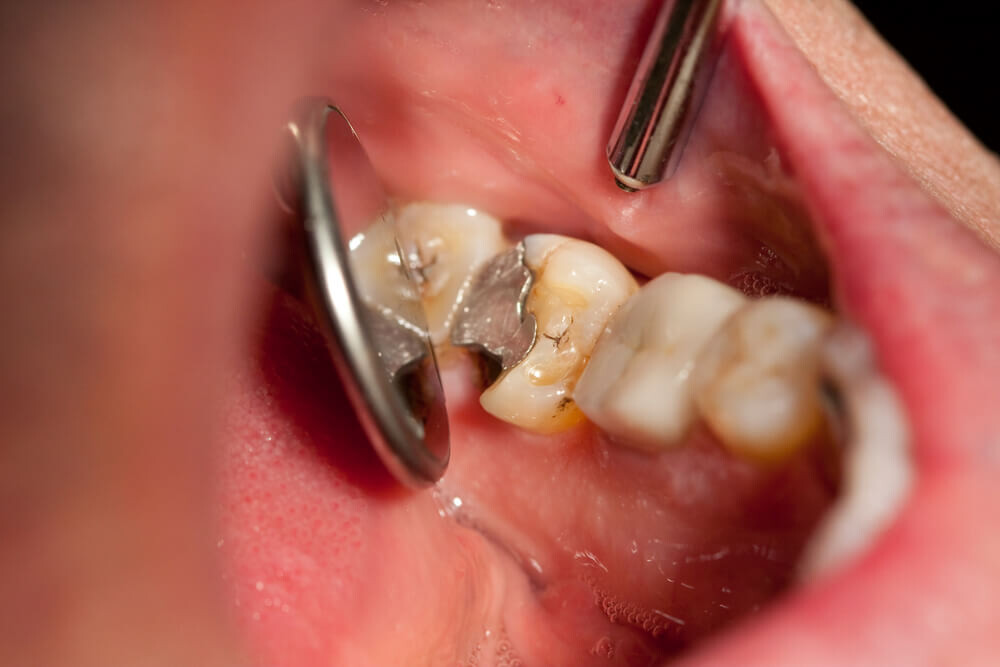

Tooth decay

As tooth decay progresses, it can reach the softer inner layers of the tooth, called dentin and pulp, resulting in sensitivity to hot, cold, or sweet foods and drinks and eventually leading to a toothache. If left untreated, tooth decay can result in an abscess, a painful infection at the root of the tooth that can cause severe pain and swelling. Adhering to your routine dental check-ups, practicing good oral hygiene, and eating a healthy diet can help prevent tooth decay and the resulting toothache.

A damaged filling

A damaged filling can cause toothache when the filling is no longer able to protect your tooth from external stimuli. When a filling is damaged, it can create an opening in the tooth, allowing bacteria to penetrate and cause an infection, leading to inflammation, swelling, and pain. Additionally, if you don’t replace the filling in time, it may cause your tooth to weaken or crack. A damaged filling may also cause sensitivity to hot and cold food and drinks.